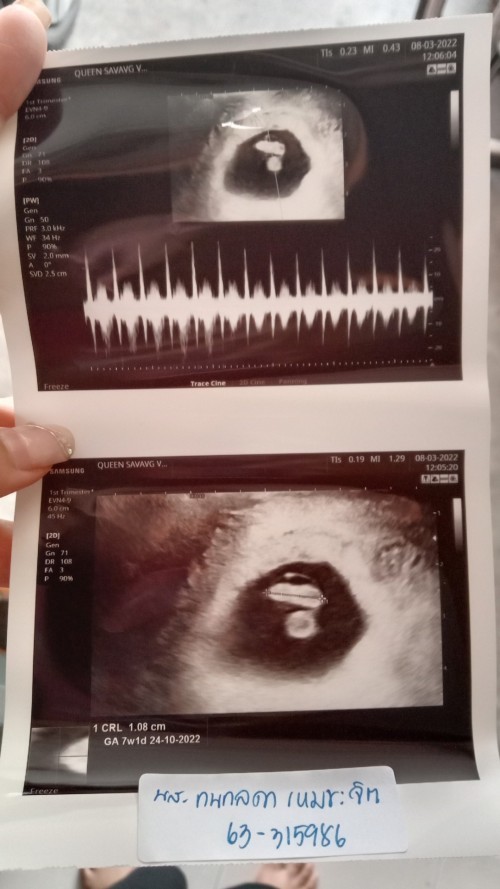

กี่ weeks ถึงจะตรวจเจอการเต้นของหัวใจลูกน้อยคะ

ตอนนี้น้อง 6 weeks 2 days

เราเจอตอน7w2d